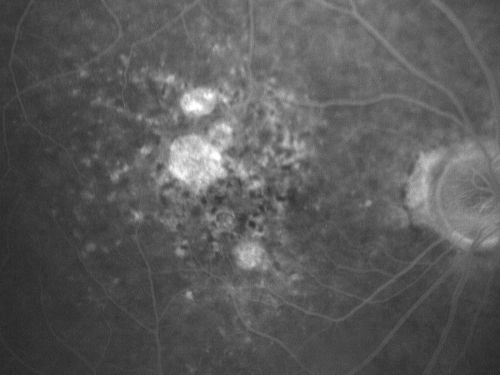

Non-Foveal Geographic Atrophy Both Eyes

81-year-old man has age-related macular degeneration in both eyes. Vision OD is 20/40, OS is 20/80.

Geographic Atrophy - Non-Foveal